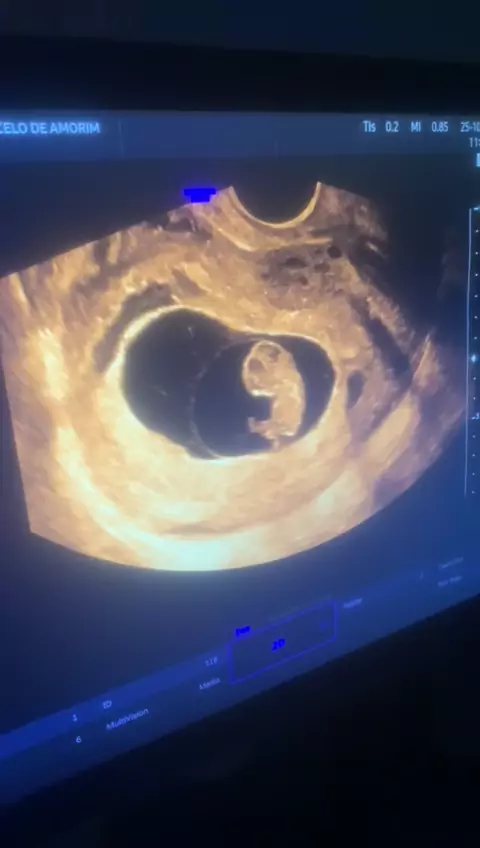

meu netinho ou netinha vovó já está contando as horas por sua chegada